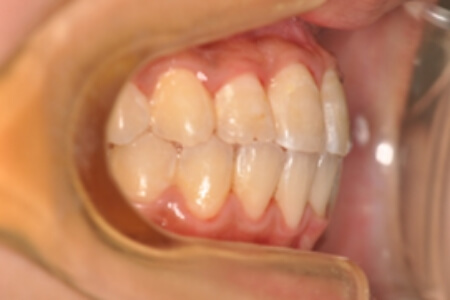

| 治療内容の詳細 | 初診時10歳の女性で、全体的ながたつきを主訴として来院されました。 検査の結果、交叉咬合を伴う、アングルⅠ級不正咬合と診断しました。 治療としては、反対咬合を改善するための装置で上顎前歯部を前方にだすと同時に上あごを広げ、セルフライゲーションブラケット装置(デーモンシステム)で歯の配列を行いました。 治療期間は2年11か月でした。 |